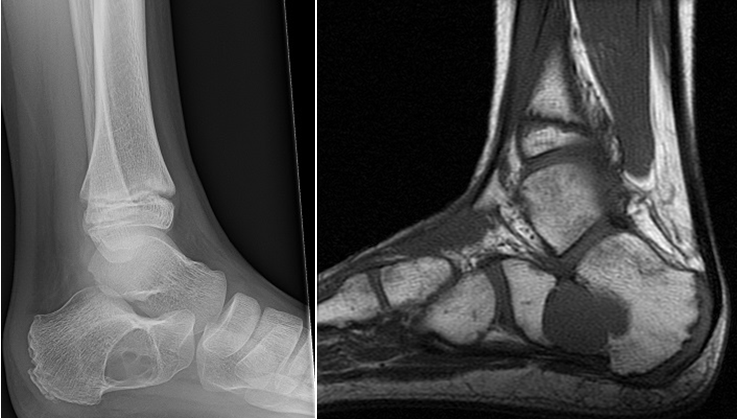

A 79-year old female presents with complaints of right hip pain for 2 months. She denies prior injury or precipitating event. The pain is made worse by lying on the affected side and occasionally hurts with hip motion. The pain is improved with NSAIDS and placing ice on the lateral aspect of her hip. Her primary care physician ordered x-rays which showed a bone lesion in the proximal femur. Her PCP was concerned she had bone cancer and ordered an MRI of the thigh to further evaluate. AP x-ray and a coronal MRI image are shown above. The patient denies a history of weight loss, fatigue, and history of cancer. On exam the patient has no pain with passive range of motion of the hip in all planes. She has pain with palpation over the greater trochanteric bursae. Motor and sensation are intact throughout the lower extremities. What is the most likely cause of this patient’s pain?